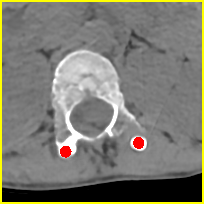

Simulation data. We generate 360,000 cases for training and 2,000 cases for testing based on clean CT images. We first resize CT images to a size of 416416 and use 640 projection angles and 641 rays for imaging geometry to simulate realistic metal artifacts (details are presented in Fig. 2).

Clinical data. We evaluate the proposed method using two clinical datasets. We refer them to DL and CL. DL represents the DeepLesion dataset [13] and CL is a clinical CT scan for a patient with metal rods and screws after spinal fusion. We randomly select 30 slices from DL and 10 slices from CL with more than 100 pixels above 3,000 HU and moderate or severe metal artifacts. The clinical images are resized and processed with the same geometry as the simulation data (see Fig. 2).